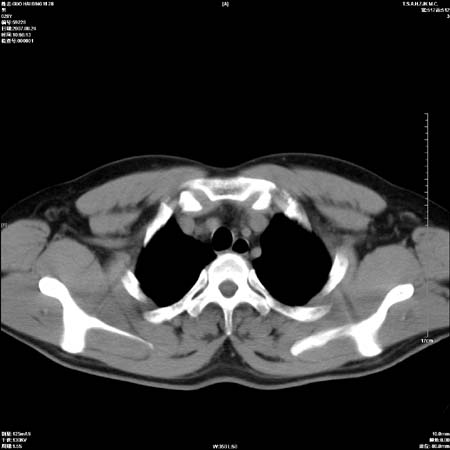

男性,28岁,体检发现左肺病变,患者只有背部隐痛感,哀哉,真不忍心下诊断啊。

左肺门区软组织肿块,左肺上叶支气管开口消失,纵隔内见肿大淋巴结,考虑左中心型肺部,可以做纤支镜取病理确认.

左肺肺门区肿块影,分叶明显,左肺上叶支气管开口受压,纵隔内见肿大淋巴结,考虑左中心型肺癌。

左侧肺门区见一块状病灶可见分叶,纵隔内及左肺门见肿大淋巴结,应该是周围型肺癌而不是中心型肺癌,原因有以下2点,1未见阻塞肺气肿和阻塞性炎症,这么大肿块如果是中心型肺癌就是未分化型或小细胞型肺癌不出现阻塞性肺不张也应该有阻塞炎症或阻塞性肺气肿,2如果是中心型肺癌临床出现最早的症状是咳嗽(此时可无任何异常影象),而此人这么大肿块只有背部隐痛是体检才发现无法解释.

直接下肺癌诊断还太早,病灶较大,估计5cm以上,但阻塞性改变及对临近纵隔及支气管侵犯不明显,密度较均匀,弓旁见一单个淋巴结,需要排除炎症性肿块及腺瘤,平滑肌瘤等。